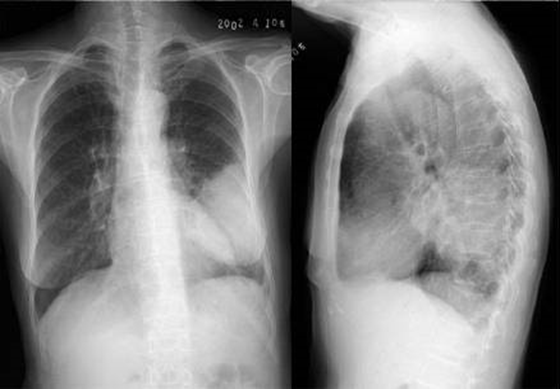

04卷-3.病史:男性,53歲,咳嗽、體重減輕4個月。診斷(本題滿分2.00分)

本題答案:C

題目解析:

【該題針對“X線-肺癌”知識點進(jìn)行考核】